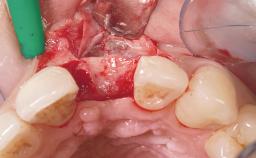

This 43-year-old male patient, a non-smoker, came to our practice because of a fracture of tooth 12 caused by a bicycle accident. Due to the combined para- and infrabony crown and root fracture, tooth extraction, and subsequent implant placement were suggested to the patient as the therapy of choice. The patient had high esthetic expectations with regard to the treatment outcome and asked for an immediate fixed provisional restoration. His individual esthetic risk profile summed up to a medium esthetic risk.

Placement Protocol Immediate implant placement

Tooth Site Maxillary incisor or canine

Socket Morphology Single-root socket

Socket Integrity Sufficient, with intact bone walls

Bone Volume Sufficient, with intact walls

Loading Protocol Immediate